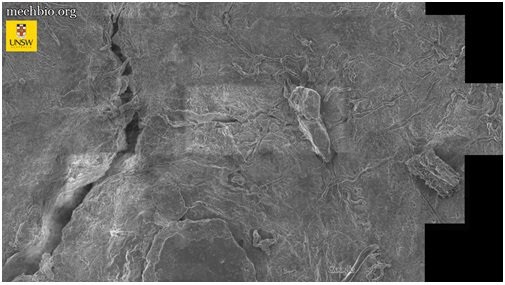

برای درک بهتر ترافیک سلولی در بدن انسان، تصاویر متعددی از استخوان لگن خاصره با استفاده از میکروسکوپ الکترونی روبشی تهیه شد؛ سپس این حجم عظیم از دادهها با استفاده از الگوریتمهای گوگل برای بزرگنمایی و کوچکنمایی بر روی بافت استفاده شد.

«نوت» تأکید کرد: برای نخستینبار، توانایی مشاهده چگونگی دریافت مواد مغذی توسط سلولهای منفرد و ارتباط آنها با یکدیگر را پیدا کردیم. این روش میتواند مسیر را برای توسعه روشهای درمانی ناشناخته و اقدامات پیشگیرانه آرتروز مفصل ران هموار کند.

در حال حاضر از این فناوری برای مشاهده بافت لگن و درک بهتر آرتروز و دردهای مفصلی مزمن در افراد سالمند استفاده میشود، اما محققان امیدوارند از این فناوری در آینده نزدیک برای بررسی سایر بافتها نیز استفاده کنند.